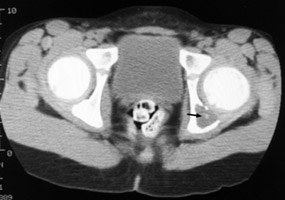

Diagnosis:Eosinophilic granuloma Discussion:Single slice of a CT scan of the pelvis with an abnormal lucent area with a sclerotic focus within it in the left hemipelvis. This sign was originally utilized to describe an unusual radiographic manifestation of Eosinophilic Granuloma. It is a round, lucent defect with a bony density, or sequestrum, in its center. This is not pathognomonic as other disease entities such as osteomyelitis can have a similar appearance. References: